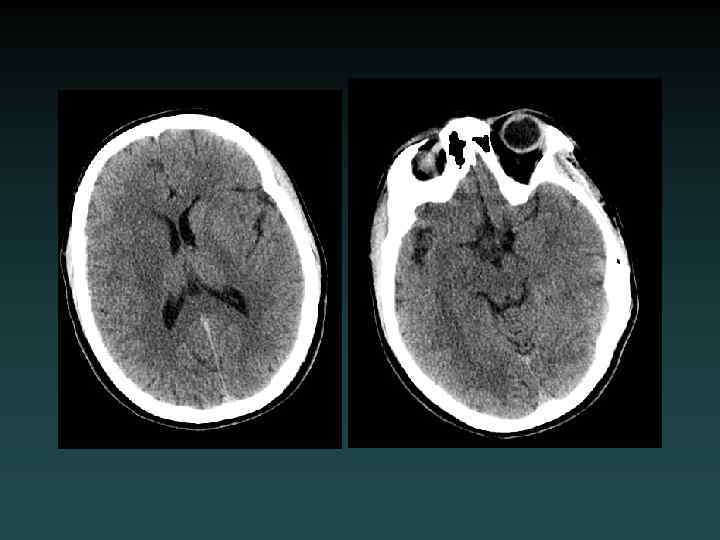

Diffuse Cerebral Edema • Grey-white interface often obscured • Sulcal effacement • Focal subtypes: – Vasogenic • Extracellular • White matter > GM – Cytotoxic • Intracellular • Grey matter > WM

Anoxic brain injury • Loss of Gray-White • Progresses with worsening edema • Pseudo. SAH • Hydrocephalus • Cisterns compressed